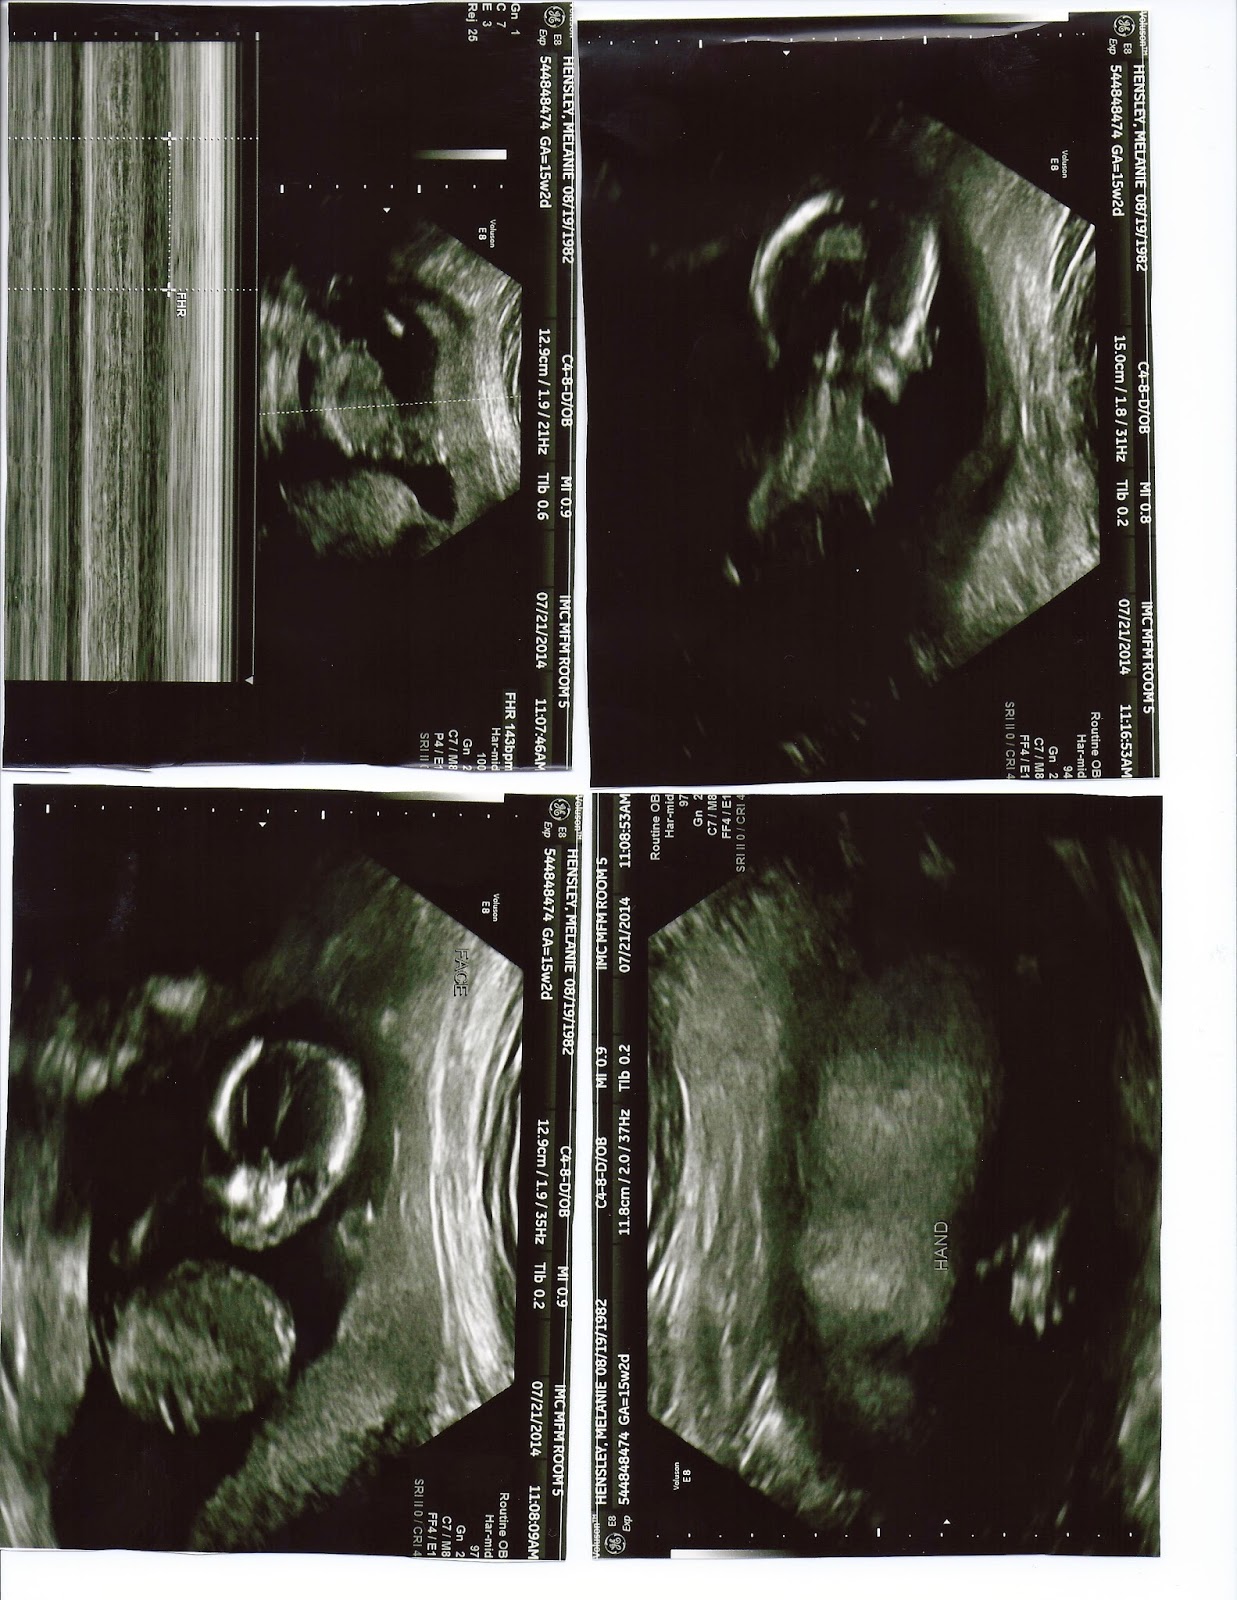

This last Monday the 25 of June we went in to look for CDH in this baby. I was only 15 weeks but they wanted to keep track and be on top of things if this nightmare again would happen. I am Thrilled to say that this baby has no sign of CDH as for now. If there is a CDH problem it will be very miner and not a problem. Still to early to see the sex. Next appointment is on August 25. At this appointment I will be 20 weeks and they will for sure be able to tell the sex. Here are some ultra sound pictures.